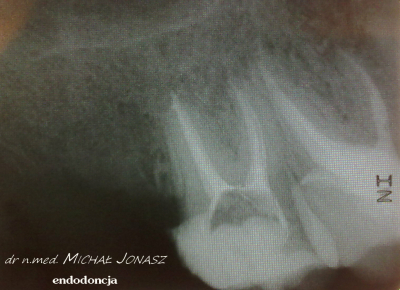

PRZYKŁADY LECZENIA KANAŁOWEGO WYKONANEGO PRZEZ NASZ ZESPÓŁ

Leczenie kanałowe staje się konieczne w przypadku zaatakowania próchnicą miazgi zęba, czyli tkanki wypełniającej jego wnętrze, która złożona jest z naczyń krwionośnych i limfatycznych oraz włókien nerwowych. W niektórych przypadkach zdarza się, że ząb nie daje dolegliwości bólowych, a jednak dochodzi w jego obrębie do nieodwracalnej bakteryjnej infekcji miazgi. W większości przypadków pacjenci wymagający leczenia kanałowego skarżą się jednak na dotkliwy ból chorych zębów. Leczenie endodontyczne jest konieczne także w niektórych przypadkach urazu zęba. Ten sposób leczenia wykorzystywany jest też czasem ze wskazań protetycznych. Zainfekowana miazga zębowa oraz występujące w niej patologiczne zmiany widoczne są niekiedy na zdjęciu radiologicznym, które wykonuje się przed zabiegiem. Dokładne oczyszczenie, chemo-mechaniczne opracowanie kanału zębowego oraz jego szczelne wypełnienie, do czego wykorzystuje się właśnie leczenie kanałowe z użyciem specjalistycznego mikroskopu, w znakomitej większości przypadków prowadzi do remisji zmian i regeneracji kości.

Przykłady odstępstw anatomicznych kanałów zębowych